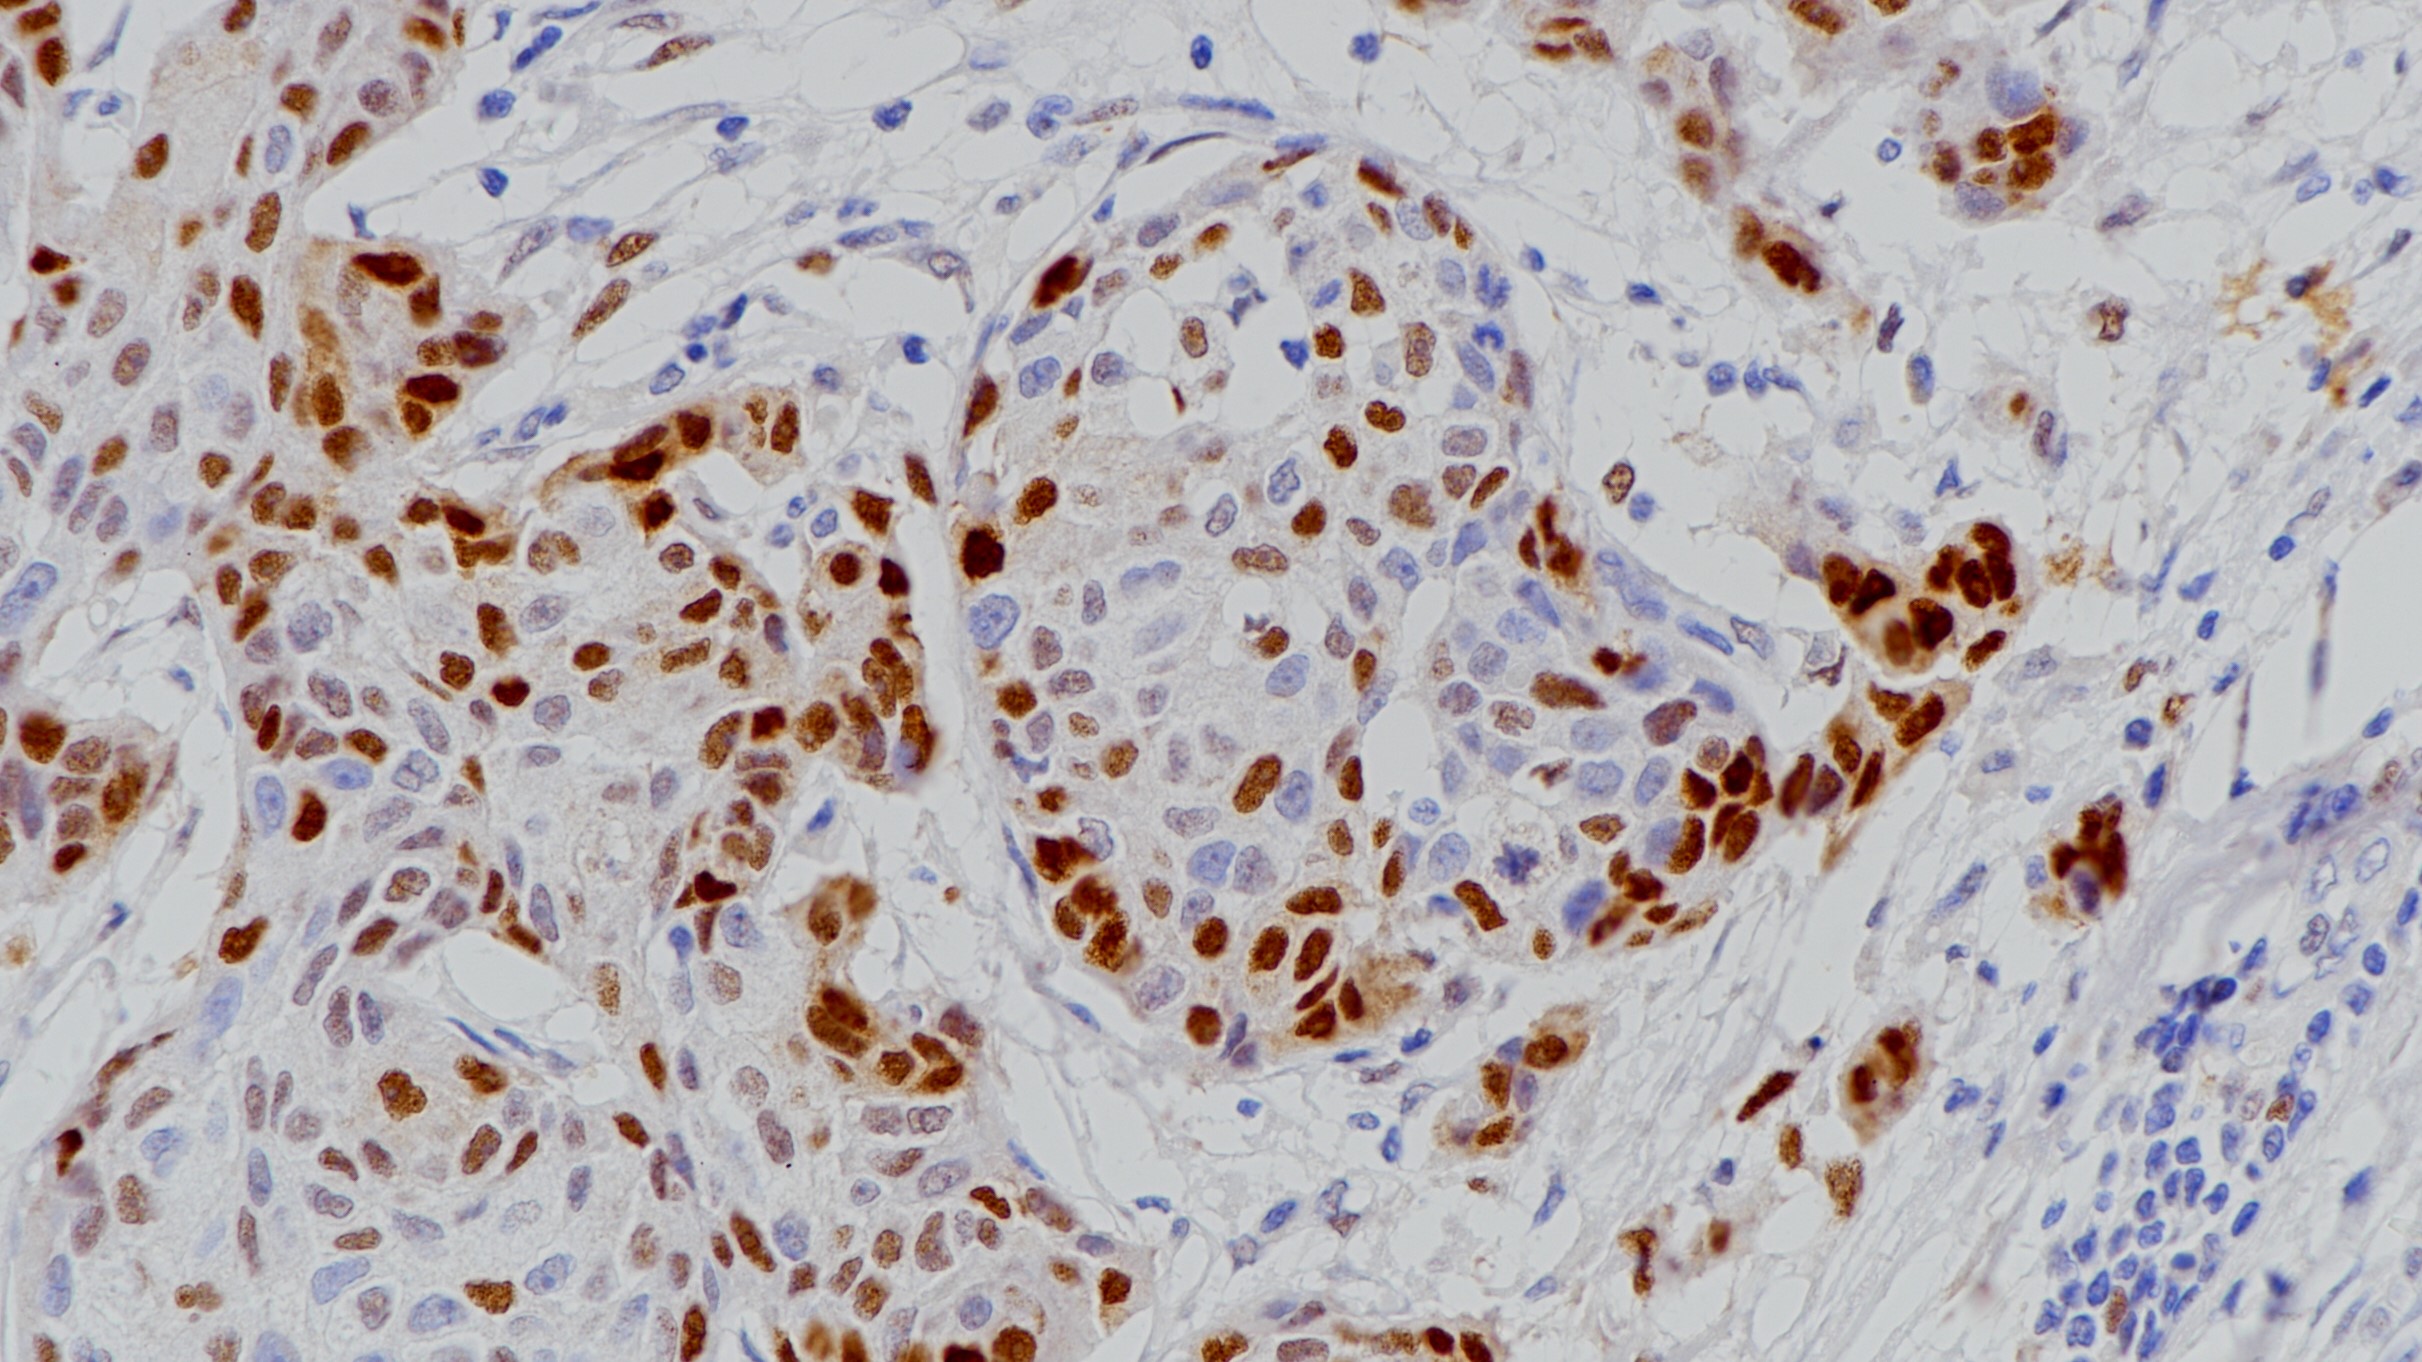

1. Clinical Implications of Claudin18.2 Expression in Patients With Gastric Cancer. [J] . Baek Jin Ho,Park Dong Jin,Kim Gyu Yeol,Cheon Jaekyung,Kang Byung Woog,Cha Hee Jeong,Kim Jong Gwang. Anticancer research . 2019 (12)

2. Expression of the potential therapeutic target claudin-18.2 is frequently decreased in gastric cancer: results from a large Caucasian cohort study. [J] . Dottermusch Matthias,Krüger Sandra,Behrens

Hans-Michael,Halske Christine,R?cken Christoph. Virchows Archiv : an international journal of pathology . 2019 (5).

3. Comparison of Claudin 18.2 expression in primary tumors and lymph node metastases in Japanese patients with gastric adenocarcinoma. [J] . Rohde Christoph,Yamaguchi Rin,Mukhina Svetlana,Sahin Ugur,Itoh Kyogo,Türeci ?zlem. Japanese journal of clinical oncology . 2019 (9).